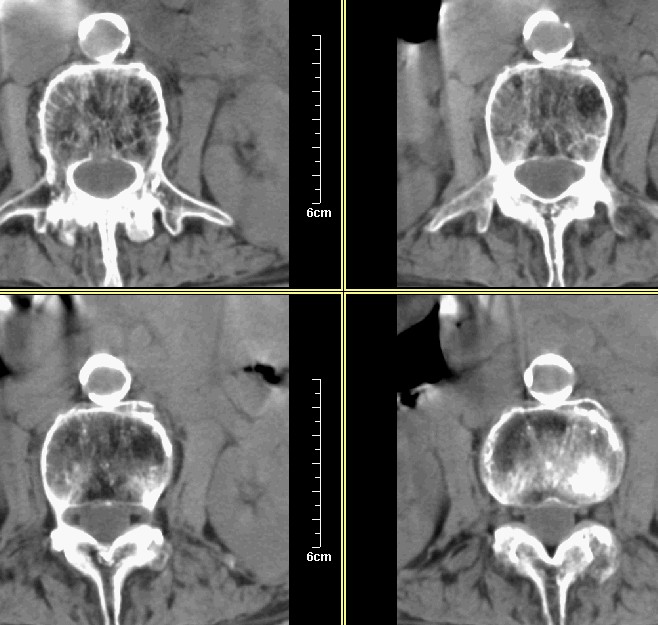

腰1-骶1 间盘及个别椎体扫描

腰3腰4椎体骨质破坏,骨密度低下,骨质疏松,少量骨小梁粗大,紊乱,椎间盘无改变,椎间隙不增宽,椎体无变形,椎旁软组织无肿胀。临床 腰痛明显。考虑:多发淋巴肉芽肿。

考虑:强直性脊柱炎伴骨质疏松症。建议做骶髂关节ct或照片。

强脊炎,再做个骶髂关节ct和抽血化验hla-27b

考虑:强直性脊柱炎伴骨质疏松症。建议做骶髂关节ct或照片